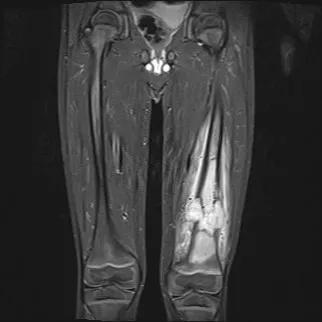

Osteosarcoma

Researchers have discovered a gene that predisposes patients to osteosarcoma, the bone tumor with the worst prognosis in children and adolescents. The SMARCAL1 gene was among nine genes associated with various cancers in a new study, the first comprehensive assessment of DNA repair genes in pediatric cancers.